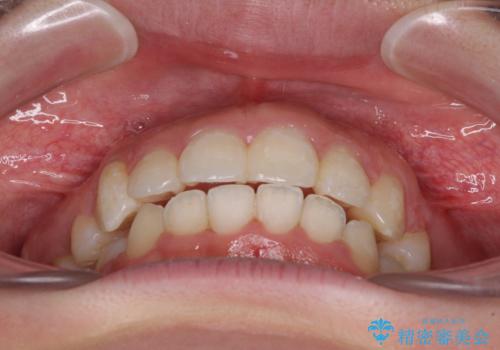

著しい叢生と顎骨のズレ ワイヤー装置による抜歯矯正

- 前歯の著しい叢生や八重歯を気にして来院された患者様です。

上下の顎がずれており、上下の正中は歯1本分の差がありました。

上下左右の小臼歯4本を抜歯し、極力正中を合わせるように矯正治療を始めていくこととしました。

咬み合わせの乱れが著しく、治療途中で一部反対咬合となってしまいました。

アンカーなどをうまく使用して、3年の期間を要してきれいに仕上げることができました。